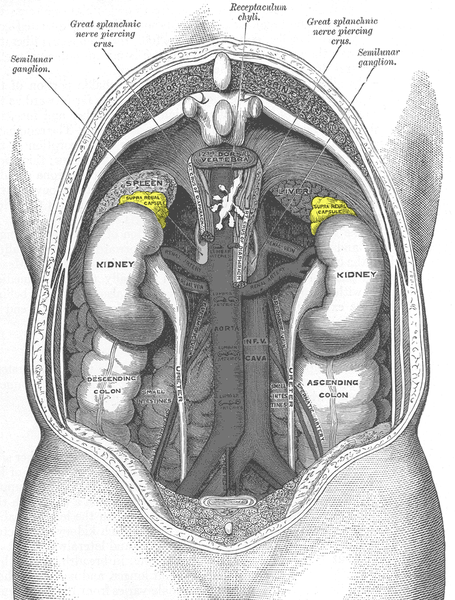

Abb. 2: Lage der Nebennieren (Ansicht von Körperrückseite!

Bildquelle: Gray1120-adrenal glands von Roxbury-de [public domain], via Wikimedia Commons

Benenne Nieren und Nebennieren am Torso. Beschreibe deren anatomische Lage.

Nieren und Nebennieren liegen im hinteren Oberbauch, d. h. hinter Magen, Darm, Bauchspeicheldrüse und Leber, leicht nach unten versetzt rechts und links der Wirbelsäule.-